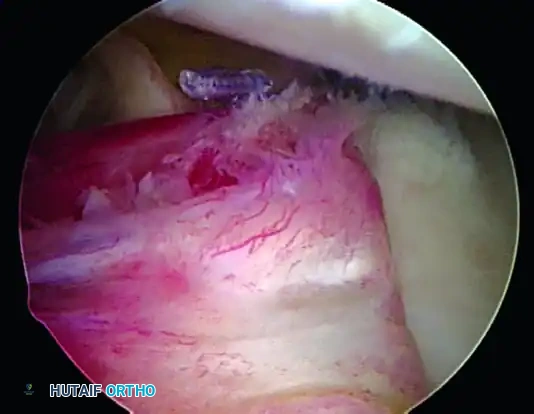

2. Posterior Capsular Plication (If Indicated)

In collision athletes or patients with multidirectional laxity, an injury to the posterior inferior glenohumeral ligament is often present. Plication of the posterior inferior capsule is highly indicated.

- Visualize from the anterosuperior portal.

- Use a rasp to freshen the posterior soft tissue to incite a healing response.

- Using a Spectrum suture passer through the posterior cannula, pass PDS sutures starting at the 6-o’clock position.

- Take a 1 cm bite of the capsule using a "pinch-tuck" technique, ensuring the needle passes up under the labrum.

- Pass multiple sutures (usually three), storing them outside the cannula to be tied later.

6. Rotator Interval Closure

If the patient exhibits baseline hyperlaxity and a significant sulcus sign that persists after the Bankart repair, a rotator interval closure is mandatory to address the superior glenohumeral ligament (SGHL) and coracohumeral ligament (CHL) laxity.

- Withdraw the anterior central cannula just outside the capsule.

- Pass a crescent Spectrum needle through the IGHL, several millimeters into the ligament, and into the joint.

- Maintain one limb outside the capsule. Retrieve the intra-articular limb using a penetrator device at the level of the SGHL.

- Tie the sutures extracapsularly using an SMC knot. Generally, two sutures are sufficient. The slight loss of external rotation is a necessary trade-off for the added inferior stability.

Completed Bankart repair with three anchors and capsule plicated inferiorly. Rotator interval is closed.